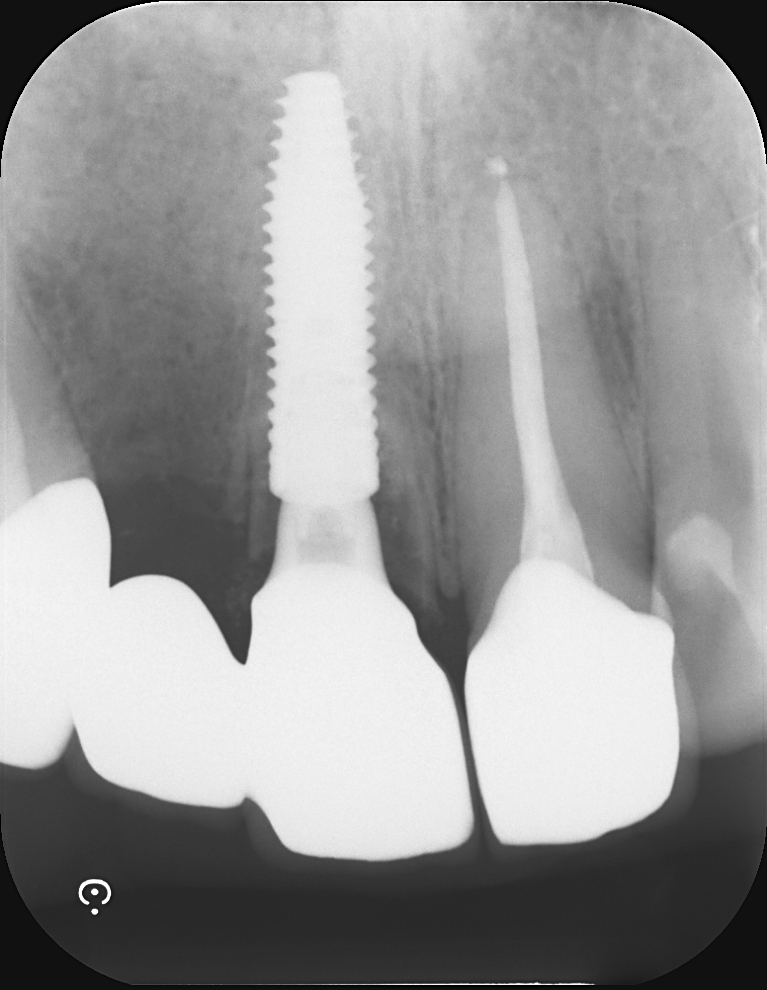

Case7

術前

術中

術後

| 治療名 | 抜歯即時インプラントとソケットリフトによる上顎臼歯部の修復症例 |

| 治療説明 |

歯の根が破折していたため抜歯が必要となり、患者さんとご相談のうえ、インプラントによる治療を選択しました。 ただし、インプラントを支える骨の高さが不足していたため、**上顎洞に骨を足す“ソケットリフト”**を併用し、安全にインプラントを埋入しました。 |

| 治療回数・期間 | 約3ヶ月 |

| 副作用とリスク |

・入れ歯や従来のブリッジと比べて、治療期間が長くなる傾向があります。 |

| 料金(税込) | 小規模GBR:110,000円 ソケットリフト:165,000円 インプラント一次手術:220,000円 二次手術:55,000円 上部構造〈セラミック〉:165,000円 合計:715,000円 |